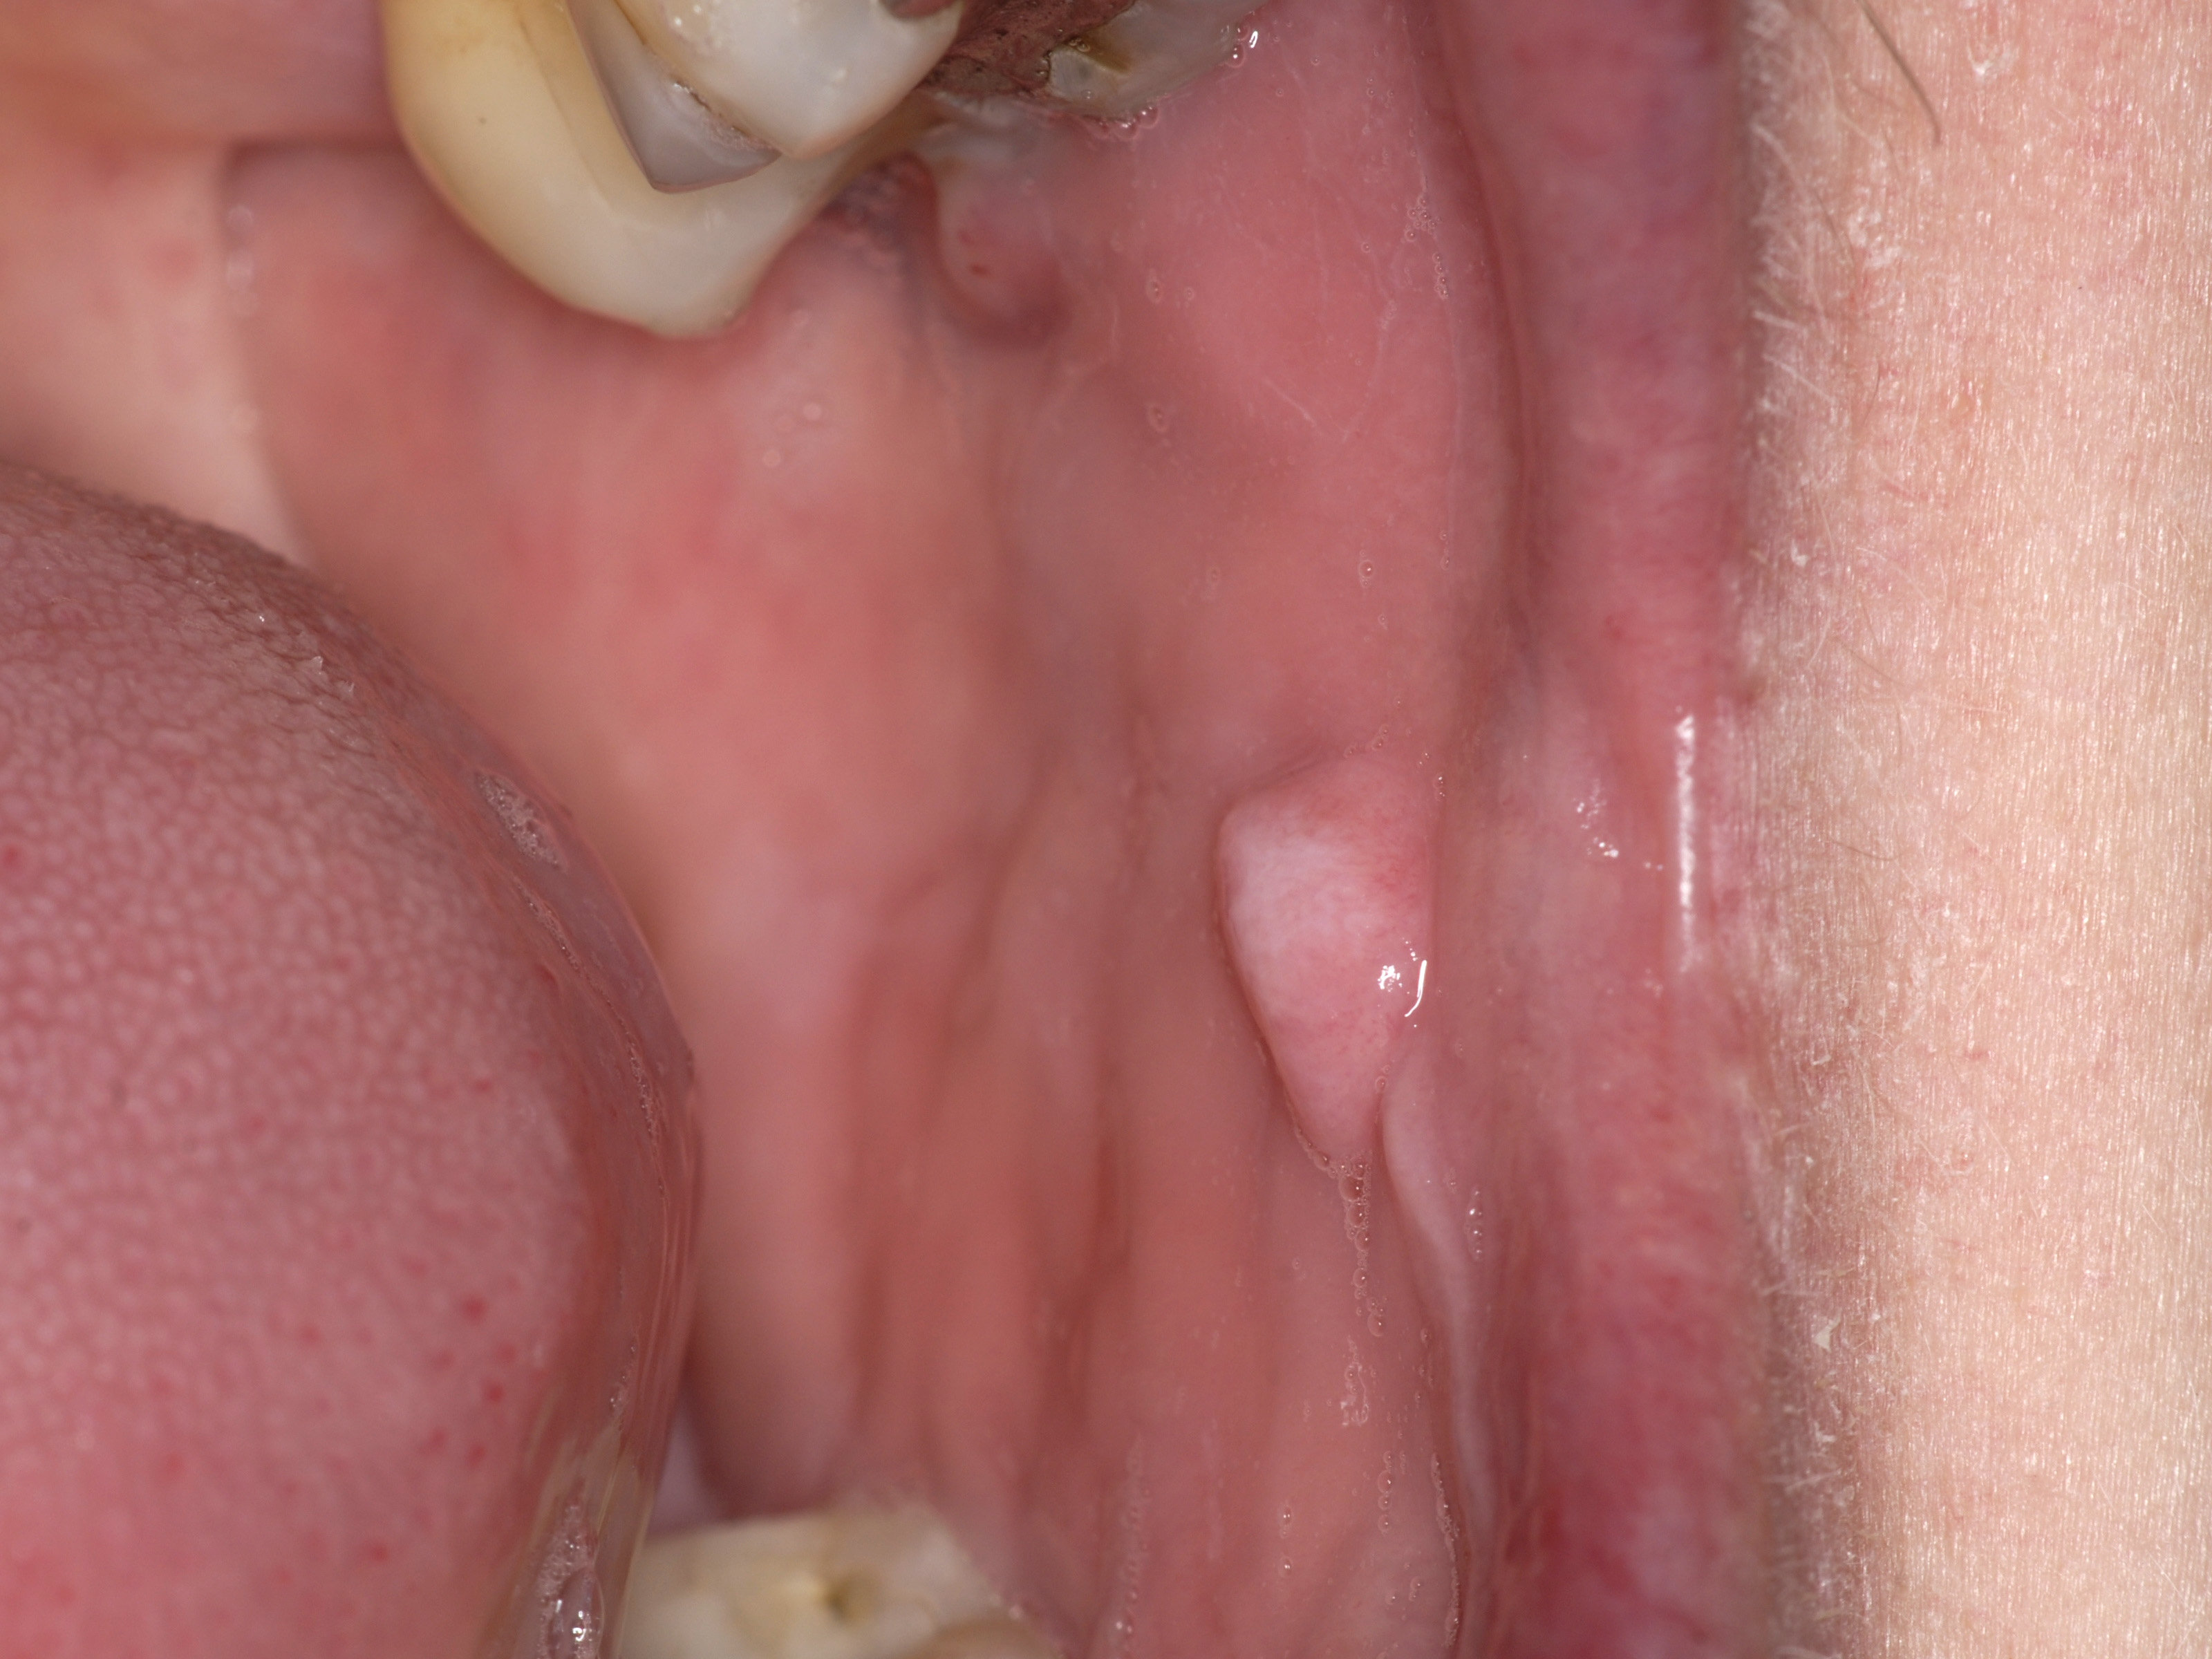

![Irritatie fibroom (click on photo to enlarge) [source: www.huidziekten.nl] Irritatie fibroom](../../../images/irritatie-fibroom-1z.jpg) |

irritatie

fibroom |

Klinisch beeld:Bolronde,

soms gesteelde roze nodus met glad oppervlak, enkele mm tot 1.5 cm groot. Kan

in de gehele mondholte voorkomen, maar vooral aan de binnenkant van de wangen

ter hoogte van de

linea alba mucosae,

waar tanden en kiezen op elkaar komen (bijtletsel), of op de lippen, de tong

of de gingiva. De kleur is gelijk aan de omringende mucosa. Kan bij de gepigmenteerde

huid ook een grijze tint hebben. Als het oppervlak hyperkeratotisch wordt ontstaat

een witte tint. Het komt vaak op oudere leeftijd voor (>60) en vaker bij

vrouwen dan bij mannen. Veroorzaakt meestal geen klachten, soms is er traumatische

ulceratie van het oppervlak.